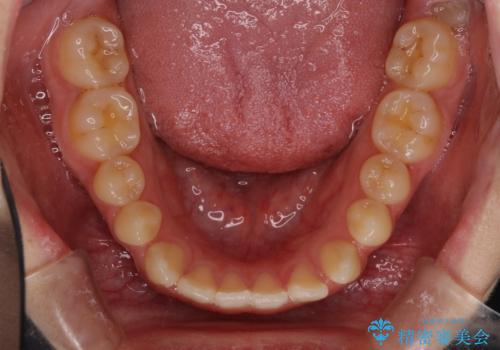

上顎骨を拡大したことで、下顎の歯列を上顎が受け入れられるようになりましたが、インビザラインでは咬み合わせを改善させることができなかったため、ワイヤー矯正にて仕上げることとしました。

ワイヤーを使用したものの、上下前歯のオープンバイトがなかなか改善されませんでしたが、患者希望により治療終了となりました。